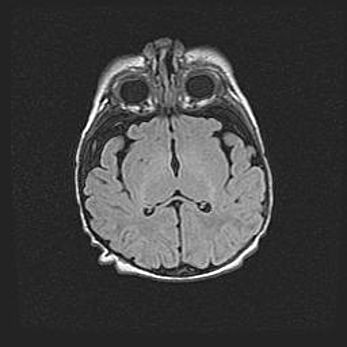

Церебральная ишемия II.

Возраст: 5 дней

Вес: 3400 г

Пол: женский

Окружность головы: 35 см

Срок гестации: 39 недель

Церебральная ишемия – это заболевание, характеризующееся недостаточностью (гипоксией) либо полным прекращением (аноксией) снабжения мозга кислородом по причине закупорки одного или нескольких сосудов. Это приводит к  что метаболическим расстройствам различной степени тяжести в тканях головного мозга, развитию коагуляционных некрозов и гибели нейронов.